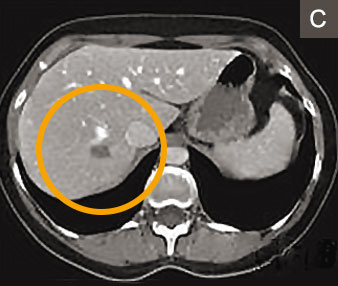

Abb 4a E 55 Jahriger Patient Mit Lebermetastasen Eines Kolorektalen Download Scientific Diagram